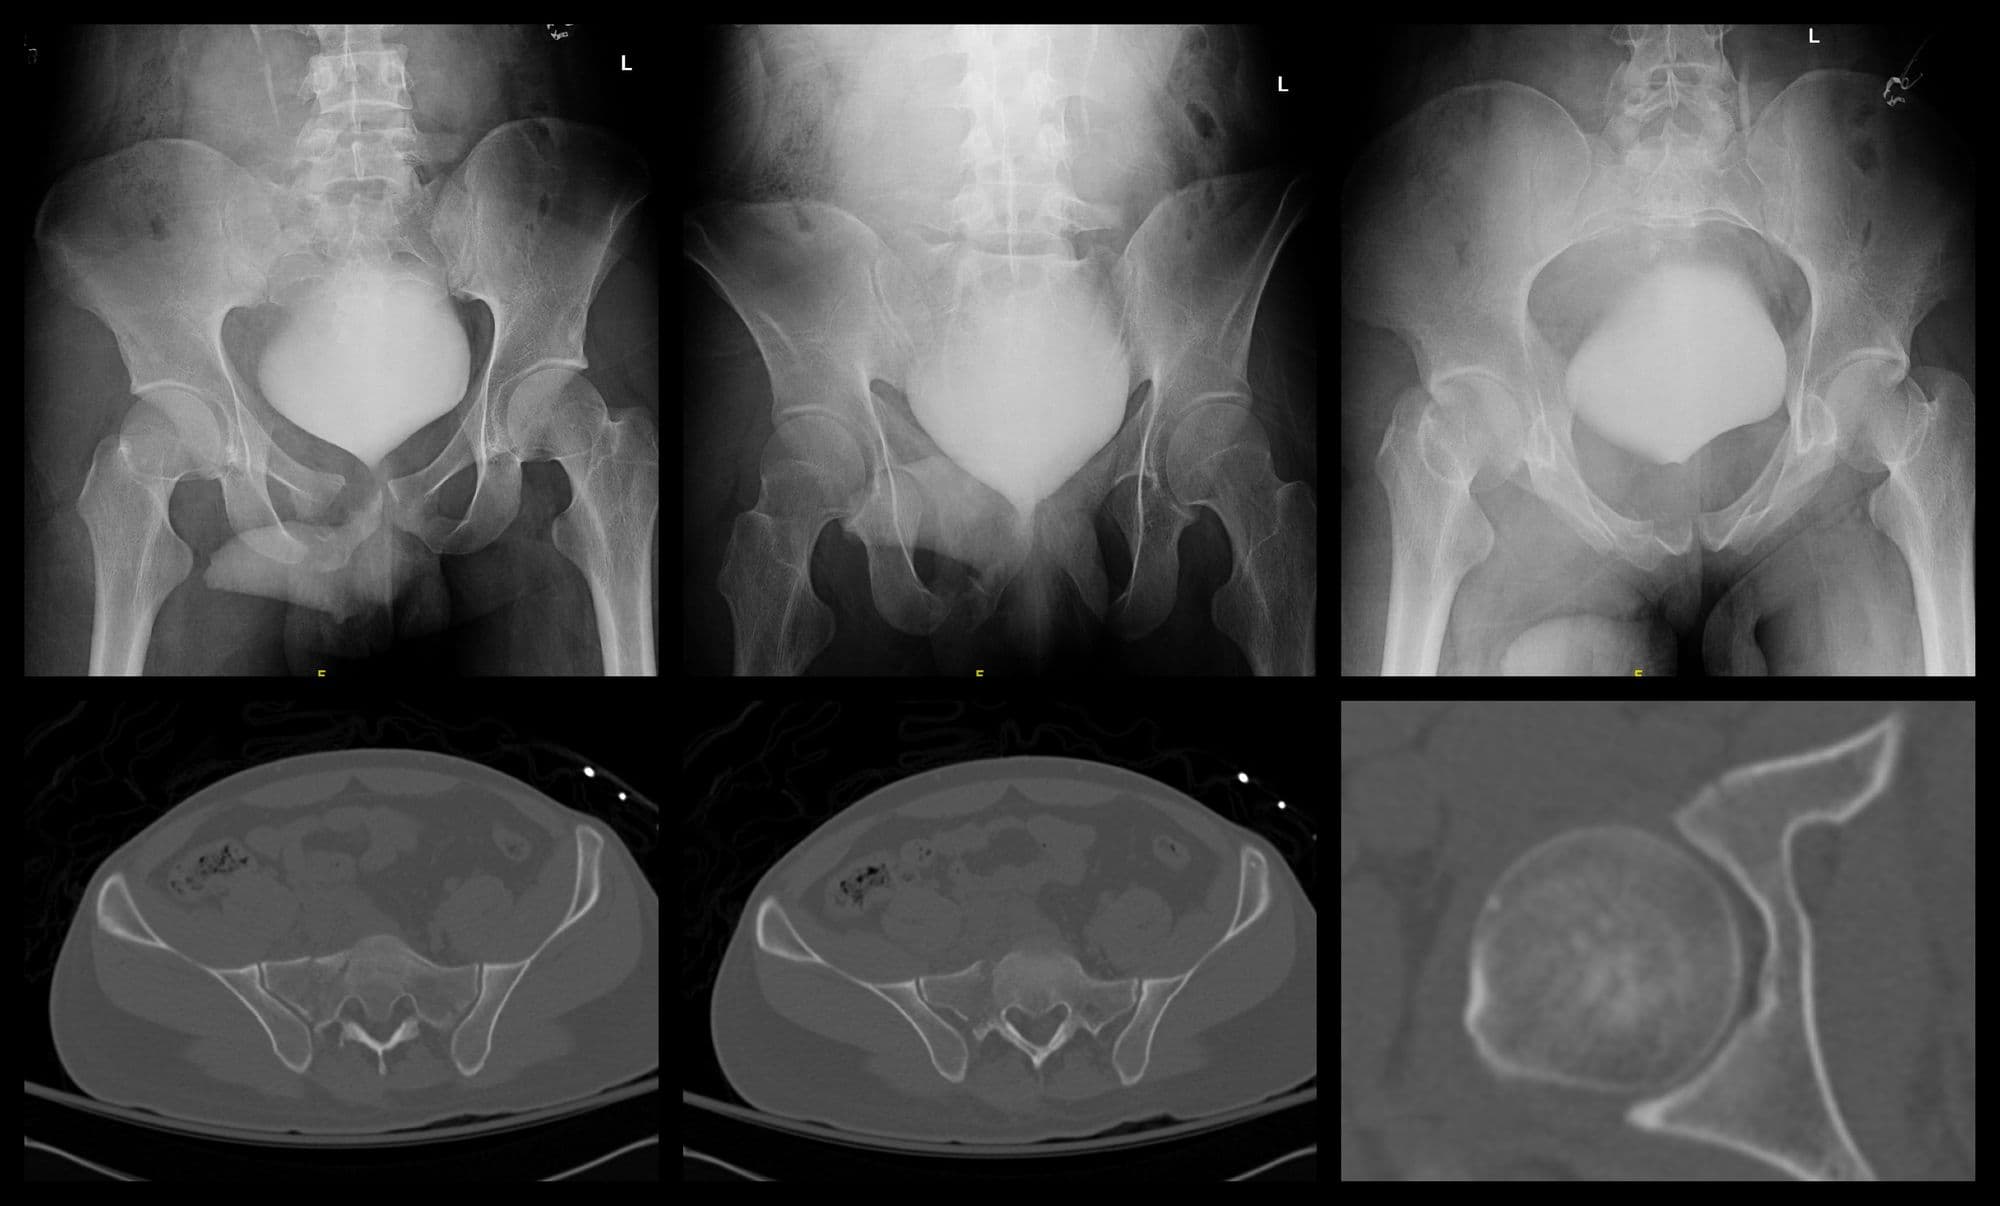

Pre-op